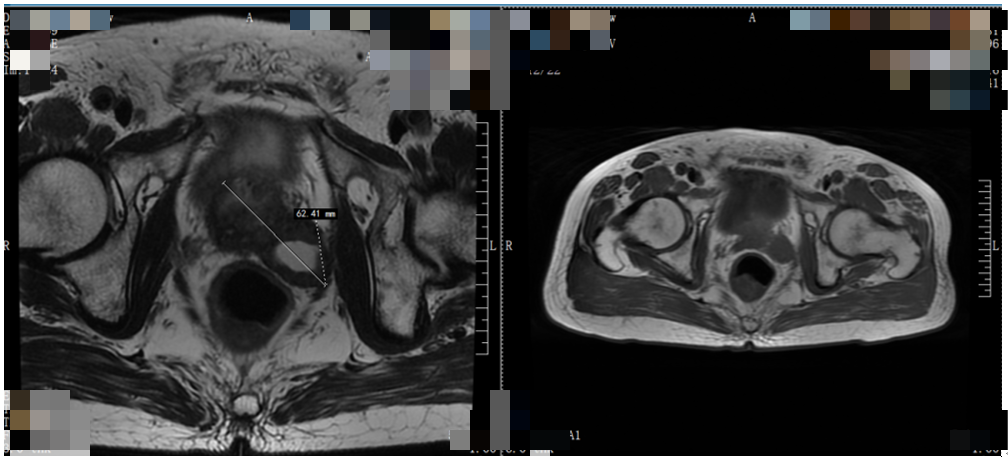

MR提示:前列腺大小、形态未见异常,右侧外周带于T2W1脂肪抑制序列呈低信号,外周带6点钟方向见结节样T2WI低信号,大小约6.6mmx14mm。精囊腺形态、信号未见异常。盆腔及双侧腹股沟未见增大淋巴结。

2020年10月14日(接受ADT+醋酸阿比特龙+泼尼松治疗后1个月):肿瘤体积明显缩小,排尿症状改善,直肠压迫症状明显缓解;T-PSA降至9.51ng/dl;复查MRI:前列腺癌伴左侧神经血管束(NVBs)侵犯,精囊侵犯可能。

2021年04月06日(接受ADT+醋酸阿比特龙+泼尼松治疗6个月):症状改善(排尿困难症状较前明显好转,现夜尿次数增多,约5-6次,尿量不多,余无特殊不适)。T-PSA降至0.06ng/dl;复查MRI:肿瘤体积与前变化不明显;复查ECT:鼻咽部、右后第11肋骨及右髂骨骨质代谢异常活跃。

影像学评估